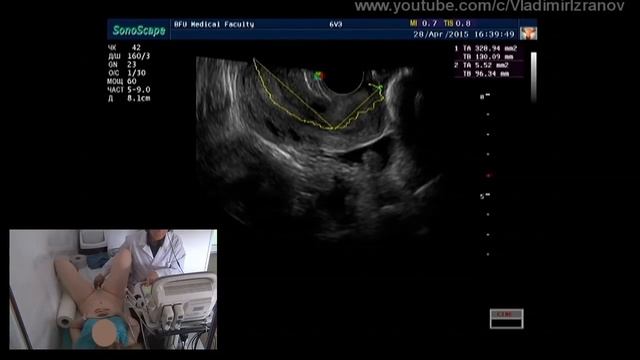

Практическое занятие: УЗИ органов малого таза у женщин (пациентка 1)

УЗИ ОБП и почек (полное исследование)